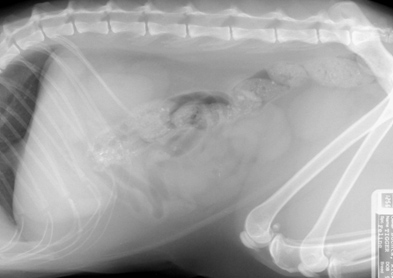

• Abdominal radiographs – What are your radiographic findings and impressions?

Figure 2: Right Lateral View